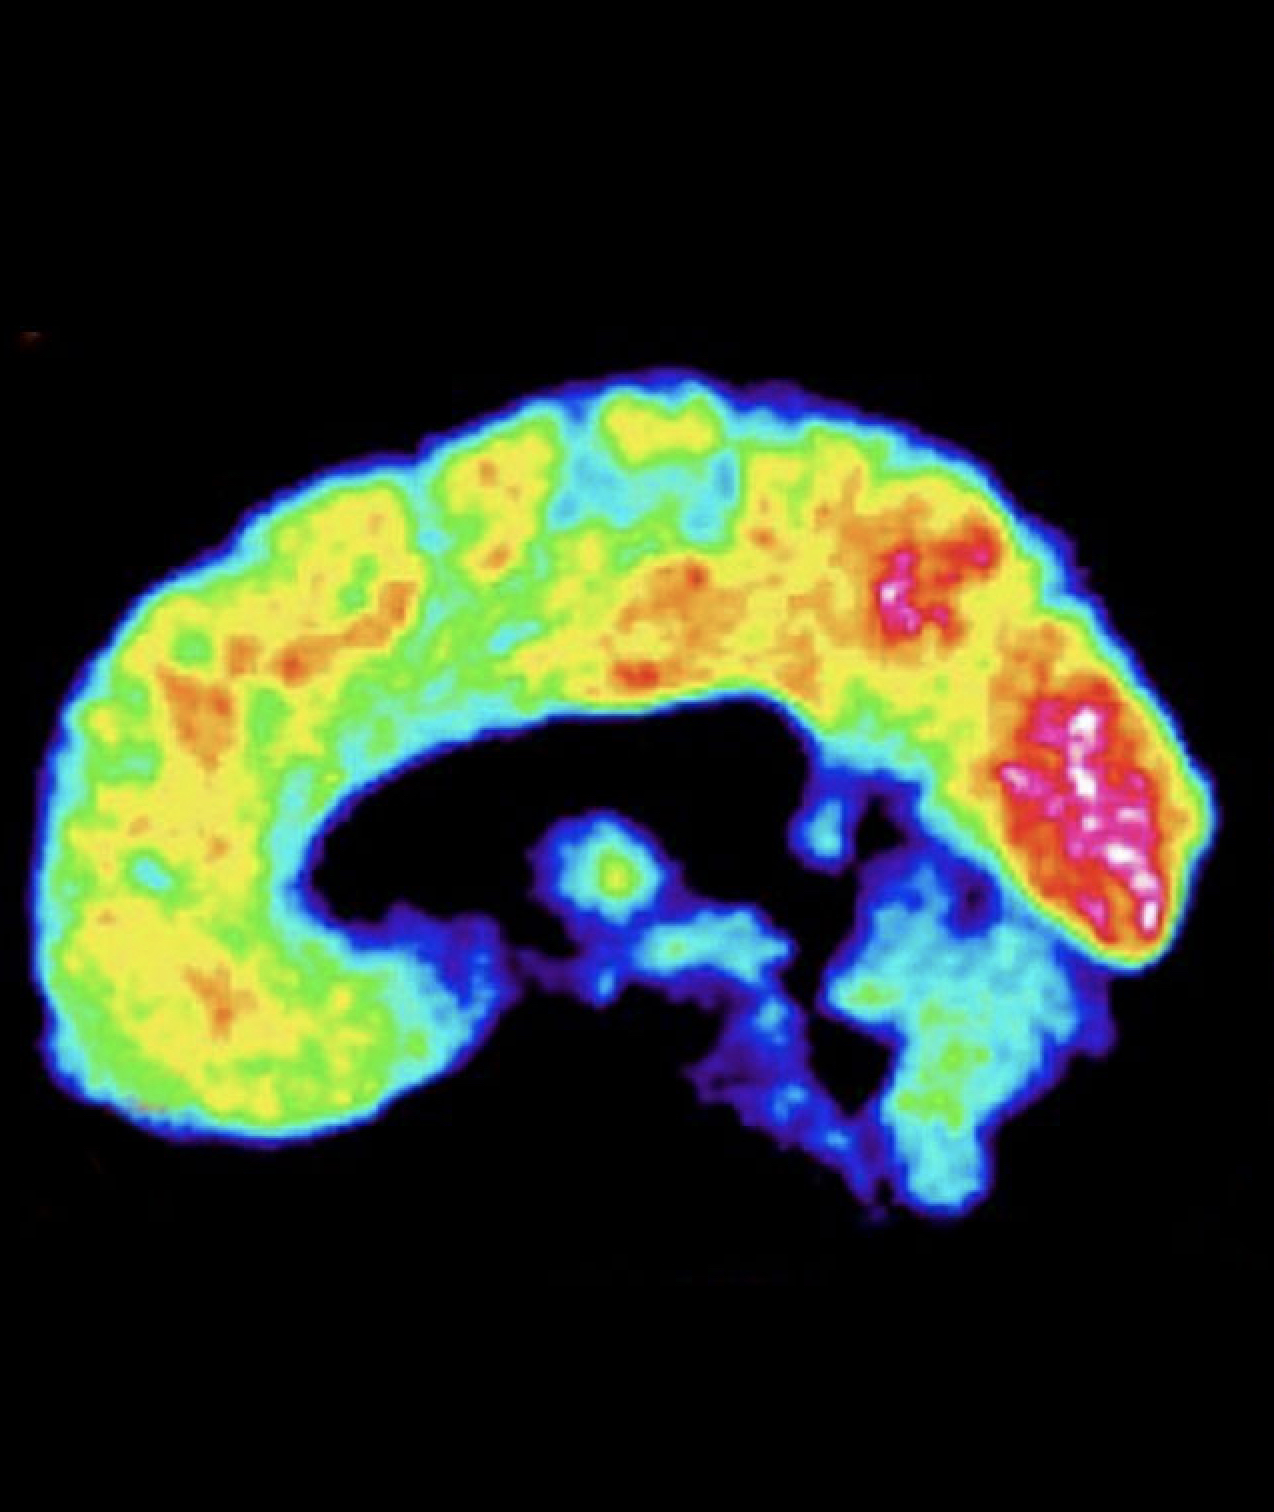

Tras reunir toda la información disponible sobre Vladímir Putin, el neurocientífico norteamericano James Fallon —profesor de Psiquiatría, Anatomía y Neurobiología de la Universidad de California— ha desarrollado la que, según él, sería una neuroimagen del cerebro del presidente de Rusia. Para explicarla mejor, Fallon —que lleva años estudiando el cerebro de los dictadores de Corea del Norte, Cuba, Bielorrusia, Venezuela y, sobre todo, Rusia— ha señalado en azul las áreas con baja actividad cerebral y en rojo, las áreas con actividad por encima de lo normal. Nos lo explica.

En todos los psicópatas esta amplia área (cortezas orbital y cingulada anterior, lóbulo frontal, amígdala…) presenta baja actividad. Es una zona que se activa pronto en el niño… si no sufre un trauma temprano. Se trastocan así los rasgos básicos de la personalidad, la conducta social y moral, el sentimiento de culpa, los impulsos agresivos, la valoración del riesgo…

El líder ruso compartiría toda la zona disfuncional del psicópata (1) y tendría, además, baja actividad en esta región de la corteza premotora. Esto eleva su control de la conducta impulsiva por encima de la media e inhibe su sentido de la empatía a la hora de tomar decisiones.

Presentaría gran actividad en estas áreas (núcleo accumbens y precúneo) implicadas en las adicciones, la necesidad de recompensa, los deseos, la memoria episódica o la cleptomanía.

La formación reticular en el tálamo es parte del mecanismo de expresión de las emociones. Fallon dice que debía de estar inactiva en el cerebro de Putin hasta hace poco. Viendo que ahora reprende a sus generales o se sienta lejos de ellos, temeroso quizá de un contagio, cree que se habría activado.